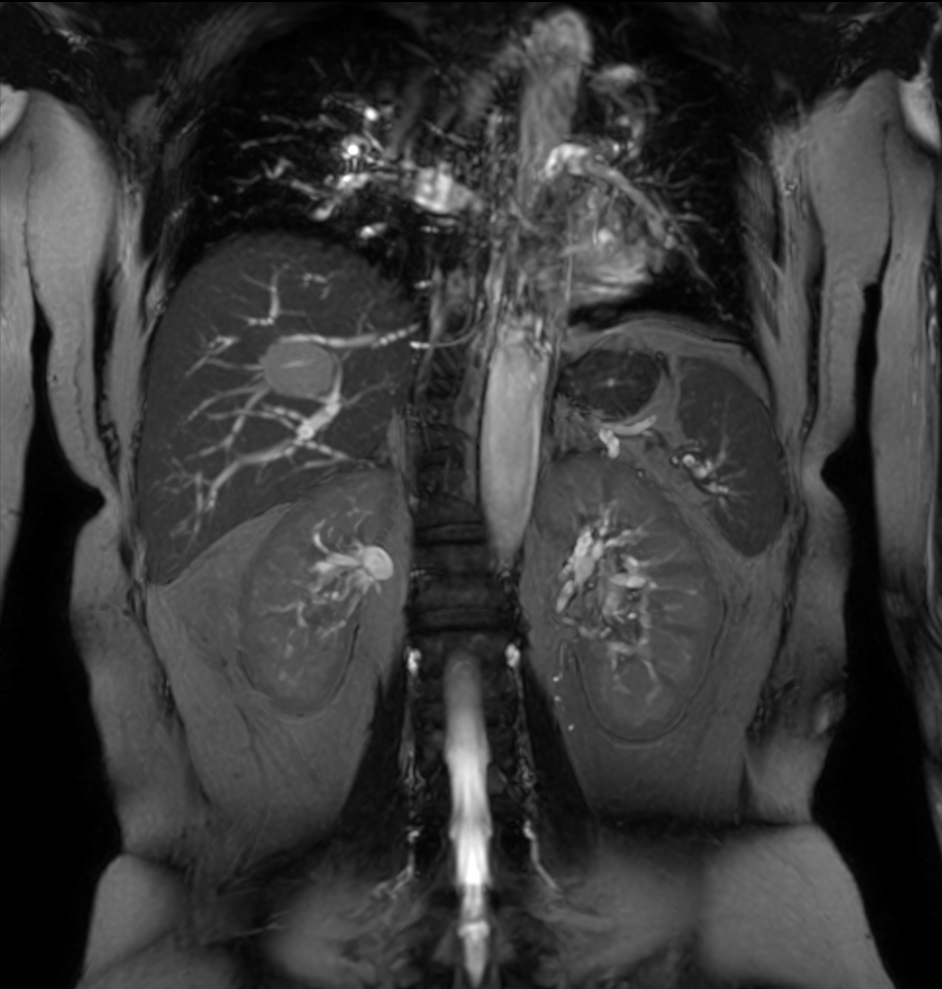

Coronal T2w SSh

Coronal bTFE

Coronal bTFE (MIP)